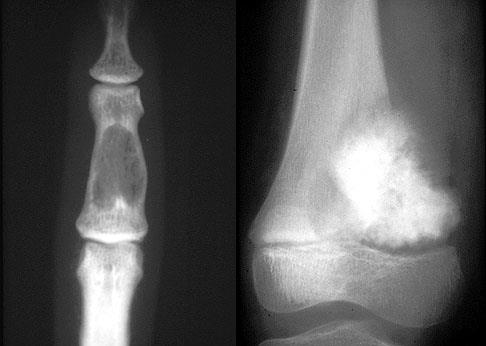

3)软骨瘤

①好发部位:40%--65%发生手部,特别是近节指骨最为多见

②好发年龄:30--40岁为好发年龄

③临床表现:患者多为无痛性肿胀,常并有病理性骨折,发生在躯干部的软骨瘤有恶变倾向

④治疗:手术治疗为主,采用刮除或病端切除植骨术,预后好

slide0065_image053